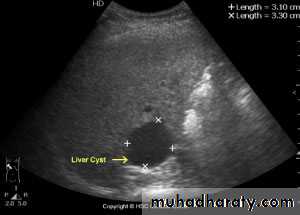

Focal masses ultrasound

Benign lesions